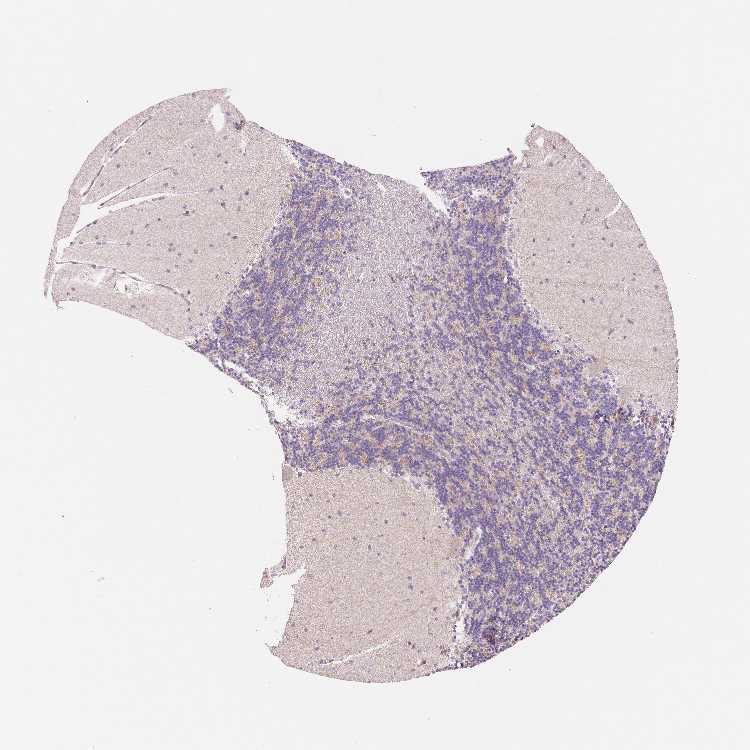

CEREBELLUM - Antibody stainingi

Antibody staining in the annotated cell types in the current human tissue is reported as not detected, low, medium, or high, based on conventional immunohistochemistry profiling in selected tissues. This score is based on the combination of the staining intensity and fraction of stained cells.

Each image is clickable and will lead to virtual microscopy that enables deeper exploration of all samples and also displays staining intensity scores, fraction scores and subcellular localization as well as patient and tissue information for each sample.

Antibody HPA051778Antibody HPA058590Antibody CAB001721

Purkinje cells Not detectedNot detectedNot detected

Cells in granular layer Not detectedMediumNot detected

Cells in molecular layer Not detectedNot detectedNot detected